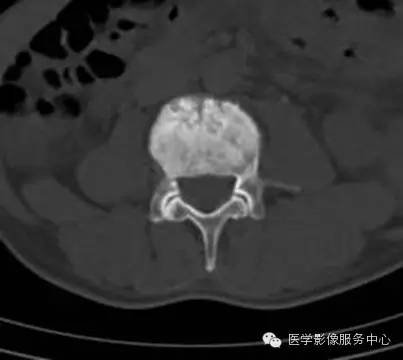

前列腺癌骨转移

前列腺癌发生骨转移的机会最多,发生率在50%~80%。国内有报道前列腺癌骨转移发生率50.9%,其中92.6%为成骨性改变,8.4%单纯溶骨性改变。转移部位以骨盆最多,其次腰椎、胸椎、颈椎、股骨粗隆、肋骨、胸骨,年龄多在60岁以上。

X线片表现:成骨性转移表现为在骨外型没有改变的骨背景上出现圆形或椭圆形致密影,有时呈地图状,边缘不规则,多数病灶可融合成片,也有病灶累及大部分或整个骨,有时在成骨性病灶边缘散在少量溶骨性破坏。密度呈棉絮样增高。前列腺癌骨转移多较典型,结合临床,诊断一般不难。

实验室检查,血清碱性磷酸酶常增高,约占80%~85%;血清酸性磷酸酶也明显增高,对诊断前列腺癌骨转移有重要价值。